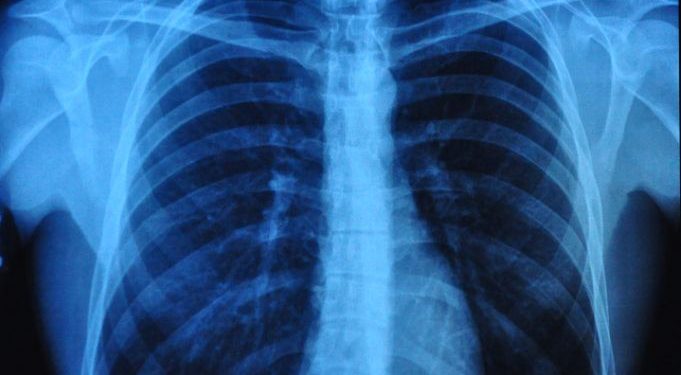

The most important symptom of asthma is shortness of breath. When the bronchioles are swollen, the mucous membranes can clog the bronchi, which leads to difficulty breathing.

People with cardiac asthma can experience similar symptoms to bronchial asthma, although they are caused by fluid accumulation in the lungs. Cardiac asthma is not as common as bronchial asthma.

Asthma can be life-threatening, so you should seek immediate medical treatment if you experience any of these symptoms. Your doctor will perform a physical exam and a lung function test. You can use a peak flow meter to detect attacks in advance.